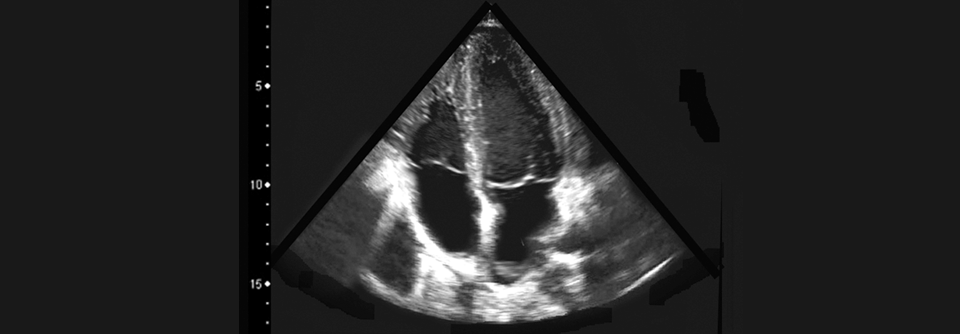

Aktuell wird die Kardiotoxizität in der S3-Leitlinie „Supportive Therapie bei onkologischen PatientInnen“ nicht berücksichtigt. Das soll sich ändern. Dipl.-Med. Gerhard Faber, Celenus Teufelsbad Fachklinik, erklärt, worauf es ankommt.

In der aktualisierten Version wird die S3-Leitlinie umfassend auf Kardiotoxizitäten eingehen – nicht nur von Zytostatika, sondern auch von neuen Wirkstoffklassen. Damit einher gehen auch Nebenwirkungen, die früher nicht oder nur wenig aufgetreten sind. „Hier schieben sich zum Beispiel auch die Entzündungen am Herzen in den Vordergrund“, erläutert der Onkologe.

Verbesserungspotenzial sieht Dr. Faber in der Zusammenarbeit von Onkolog:innen und Kardiolog:innen. So sei ihm keine Tumorkonferenz bekannt, an der regelmäßig auch ein Kardiologe bzw. eine Kardiologin teilnimmt. Dafür reichen vermutlich auch in Zukunft die Kapazitäten nicht aus. Darum sei es umso wichtiger, Patient:innen zuverlässig zu identifizieren, die von einer Mitbetreuung in der Kardiologie profitieren würden.